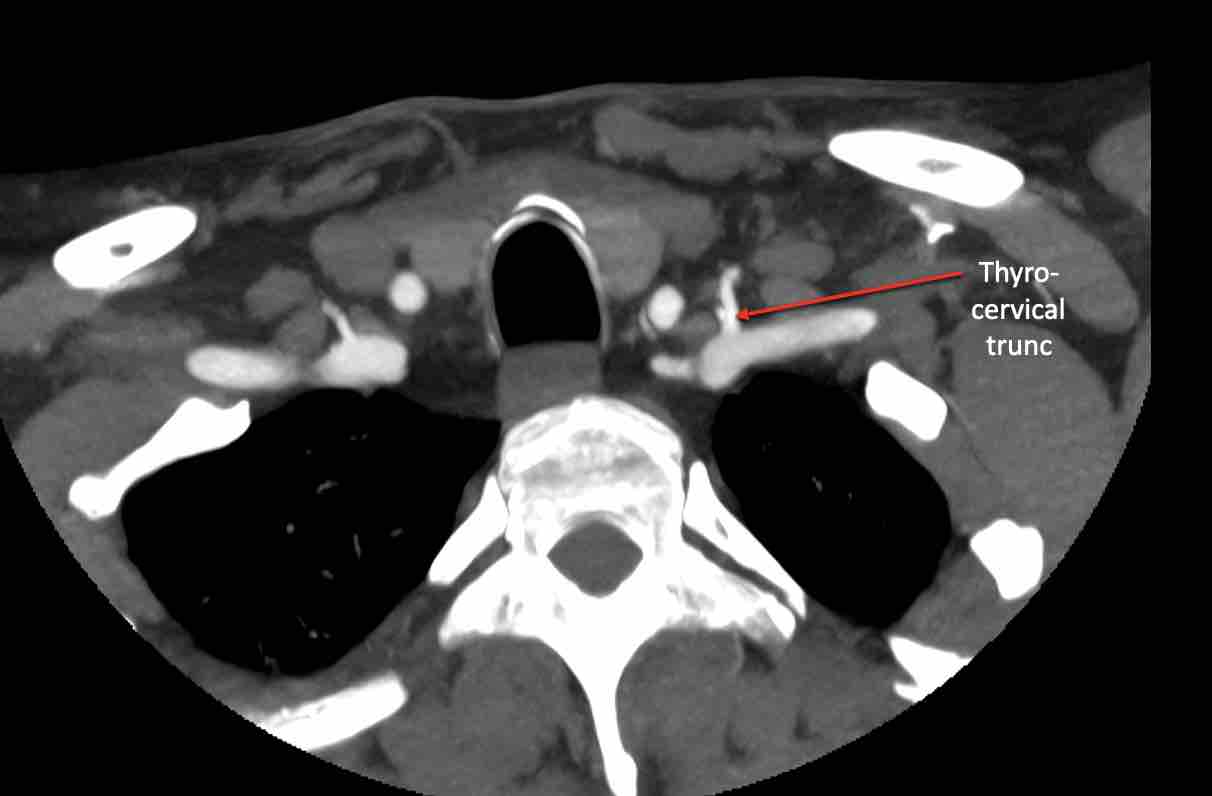

Động mạch cổ ngang

Cuộn qua các hình ảnh để xem giải phẫu của động mạch cổ ngang.